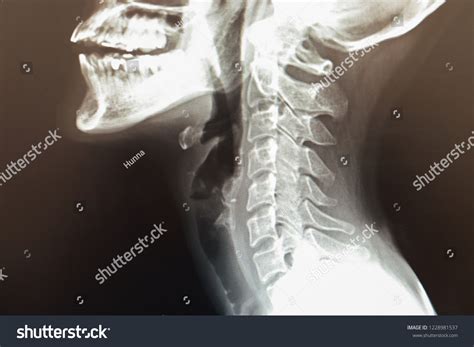

Understanding the importance of a Normal Cervical MRI is crucial for anyone who has undergone or is considering this diagnostic procedure. A cervical MRI, or magnetic resonance imaging, is a non-invasive medical test that uses magnetic fields and radio waves to produce detailed images of the cervical spine. These images help healthcare providers diagnose a variety of conditions affecting the neck, including herniated discs, spinal stenosis, and tumors.

A Normal Cervical MRI involves the use of a powerful magnetic field, radio waves, and a computer to create detailed images of the cervical spine. This area includes the seven vertebrae in the neck, which support the head and allow for its movement. The procedure is painless and does not involve radiation, making it a safe option for many patients.

The results of a Normal Cervical MRI are interpreted by a radiologist, who specializes in medical imaging. The radiologist looks for any abnormalities in the cervical spine, such as:

• Herniated discs, where the soft center of a disc pushes through a tear in the outer ring.

• Spinal stenosis, a narrowing of the spinal canal that can compress the spinal cord or nerves.

• Tumors or other masses that may be pressing on the spinal cord or nerves.

• Infections or inflammation that may be affecting the cervical spine.

The radiologist’s report is then sent to the referring healthcare provider, who will discuss the findings with the patient and recommend appropriate treatment options.